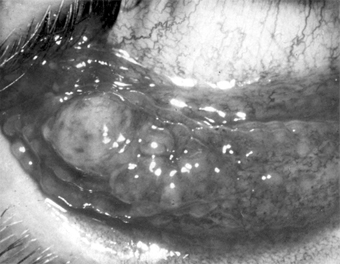

Lymphangiectasis is characterized by localized small, clear, tortuous dilations in the conjunctiva. They are merely dilated lymph vessels, and no treatment is indicated unless they are irritating or cosmetically objectionable. They can then be cauterized or excised (Figure 5-23).

Figure 5-23

Figure 5-23: Conjunctival lymphangiectasis. Note the clear tortuous dilations in the conjunctiva.